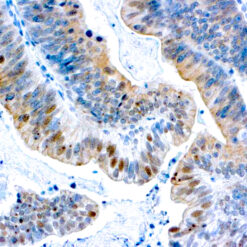

CD79a Antigen (HM47/A9)

This antibody is specific to human CD79a antigen complex, consisting of two polypeptides non-covalently associated with membrane-bound immunoglobulins on B cells. This complex of polypeptide and immunoglobulins constitute the B cell antigen receptor. The two components of this complex are designated CD79a and CD79b. The CD79a antigen appears at the pre-B cell stage, early in maturation and persists until the plasma cell stage. The CD79a antigen is found in majority of acute leukemias of precursor B cell type, in B cell lines and B cell lymphomas.

| Positive Control Tissue | Tonsil |